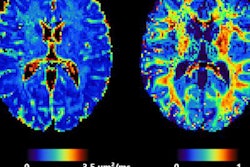

There's currently a "significant evidence gap" for the use of many available automated volumetric MRI reporting applications in diagnosis of dementia, according to research led by investigators in the U.K. and the Netherlands.

With the growing number of commercial quantitative volumetric reporting applications, the researchers sought to assess the available evidence base to help neuroradiologists make informed decisions on adopting these tools in clinical practice.